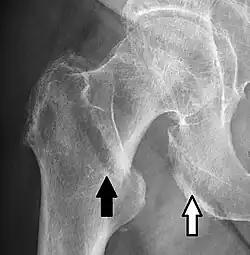

- A hip fracture (black arrow) next to a skin fold (white arrow).